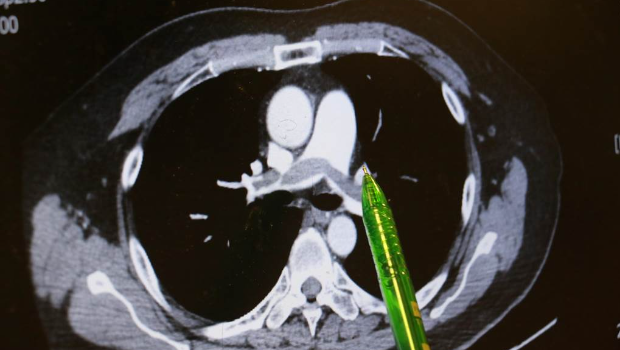

病人肺部兩側大片彌漫的血栓。

▲病人肺部兩側大片彌漫的血栓。臺中慈濟醫院提供

謝姓男子不煙不酒,他自述上班久坐、在家也習慣久躺沙發,回想發病當天走樓梯時,短短一層樓竟像爬長陡坡,路過同事見他喘不過氣、唇色發綠、冷汗直冒,催促緊急就醫。臺中慈濟醫院急診醫師檢查發現患者血氧飽和度指數極低,電腦斷層顯示雙側肺動脈都有大塊血栓,會診心臟內科主任林茂仁確認是“雙側肺栓塞(Pulmonary embolism)”。

林茂仁說明,患者兩側肺葉彌漫大片血栓,屬于臨床典型而嚴重的“肺栓塞”,幸好他馬上到急診就醫,還主述一周前曾出現“單側小腿腫脹”的重要訊息,再透過相關檢查,幫助醫師快速查出病因。由于患者血液檢查發現具有家族性先天凝血因子異常,顯示體質天生比一般人有更多發生血栓的機會。